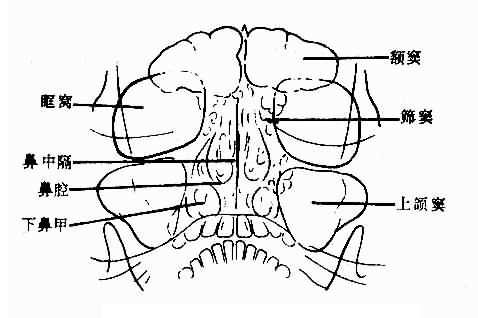

平片是检查鼻窦的基本方法。一般取坐位,鼻窦显示较好,且可查出鼻窦内积液。常用枕颏位,可显示两侧额窦、筛窦、上颌窦及鼻腔。正常所见,见图5-2-4。

图5-2-4 正常鼻窦(枕颏位)

额窦:多呈扇形,腔内可有骨性间隔。窦腔透明度因骨壁各部厚薄不同而不均。大小及形状个体差别较大,两侧多不对称。一侧或两侧可不发育或发育不良。

筛窦:呈蜂窝状居鼻中隔两侧和眼眶之间,其外壁为眼眶内壁。枕颏位上,蜂窝上部为前组窦,蜂窝下部为后组筛窦。蜂窝小房透明,间隔清晰、锐利,两侧多较对称。

上颌窦:居眶下方,鼻腔外侧,呈尖向下的三角形。上颌窦较透明。如嘴唇较厚,与下部重迭,可使窦腔下部密度较大,鼻翼较大,可从内壁上中部向窦腔内突入呈半圆形软组织重迭影,两侧对称,不难确认。岩骨可投影于窦腔下部,使窦腔下部密度高,不可误认为液面。两侧上颌窦的大小、形状和透明度多对称,有时一侧较小,透明度较低。

蝶窦:用颏顶位观察。呈近似椭圆形透明影,窦腔清晰、锐利。大小及外形个体差别较大,两侧可不对称。

鼻腔:鼻腔透明,鼻中隔为纵行致密带影,近于中线,多稍向一侧弯曲,上鼻甲不易显示,中鼻甲骨片垂直,下鼻甲骨片卷曲。鼻甲粘膜厚,由气体衬出。鼻甲大小个体差别较大,两侧可不对称。